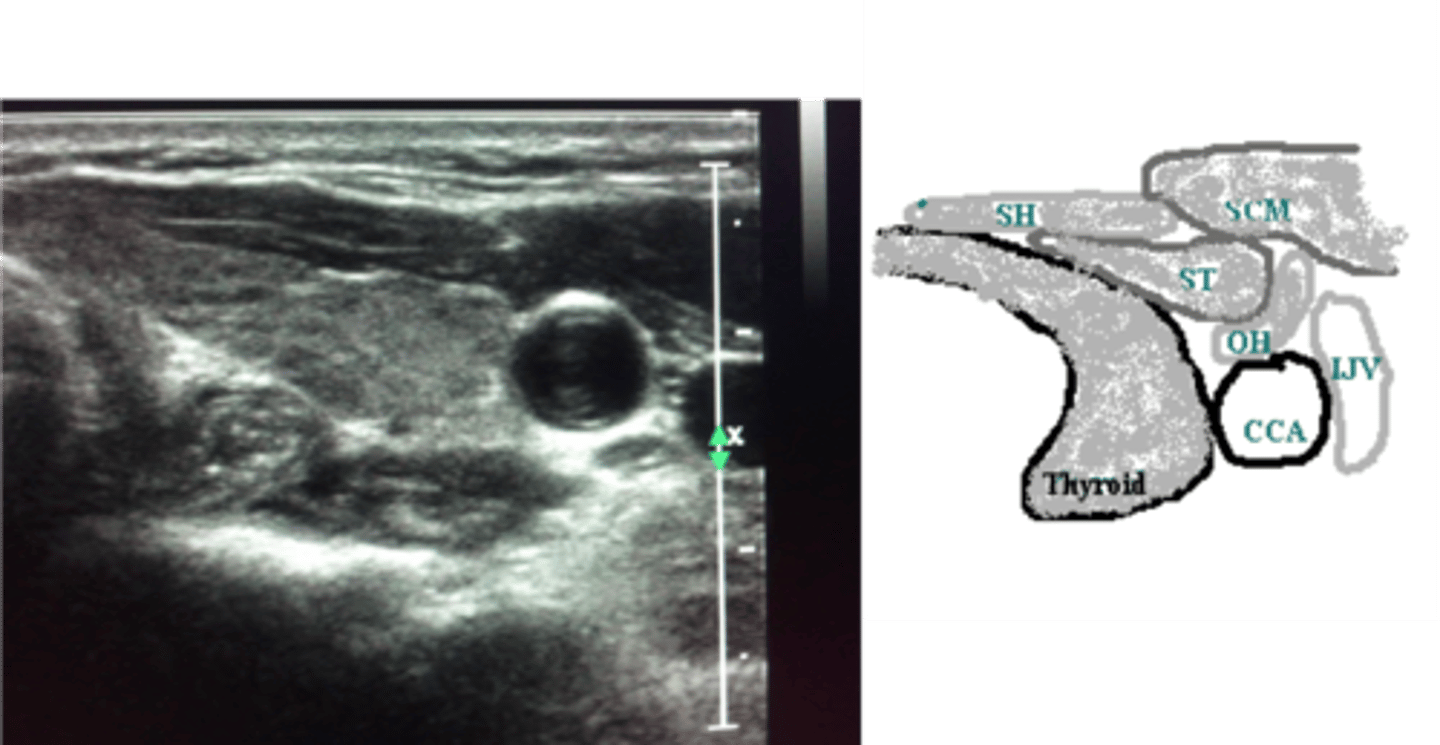

Muscles of the neck - Longus colli muscles:

-Located on the _____ surface of the vertebral column

-Lie adjacent to the ____ and _____ to the thyroid lobe and CCA

-May be mistaken for an enlarged _____

-Located on the anterior surface of the vertebral column

-Lie adjacent to the trachea and posterior to the thyroid lobe and CCA

-May be mistaken for an enlarged parathyroid gland

Muscles of the neck - Sternocleidomastoid Muscles:

-_____ and _____ neck muscles

-Located _____ to the thyroid lobes, sternohyoid muscle and sternothyroid muscle

-Lateral and superficial neck muscles

-Located lateral to the thyroid lobes, sternohyoid muscle and sternothyroid muscle

Muscles of the neck - Strap Muscles:

-A collective group of long flat neck muscles

-Located _____ and _____ to the thyroid gland

Include the:

-Sternothyroid - located directly _____ to the thyroid gland

-Omohyoid - located _____ to the sternothyroid muscles

-Sternohyoid - located _____ to the sternothyroid muscles

-Located anterior and lateral to the thyroid gland

-Sternothyroid - located directly superficial to the thyroid gland

-Omohyoid - located lateral to the sternothyroid muscles

-Sternohyoid - located anterior to the sternothyroid muscles

Common carotid arteries:

-Left originates from the _____

-Right arises from the _____

-Ascend the _____ aspect of the neck

-Lie _____ to the internal jugular vein and _____ to the thyroid lobe

-Course deep to the _____ muscles

-Typically, no _____

-Bifurcate into the _____ and _____ carotid arteries

-Left originates from the aortic arch

-Right arises from the innominate (brachiocephalic) artery

-Ascend the anterolateral aspect of the neck

-Lie medial to the internal jugular vein and lateral to the thyroid lobe

-Course deep to the sternocleidomastoid muscles

-Typically, no branches

-Bifurcate into the external and internal carotid arteries

Location - Thyroid Lobes:

-_____ and _____ to the corresponding CCA and IJV

-_____ and _____ to the SCM and strap muscles

-_____ to the longus colli muscle

-_____ to the trachea and esophagus

-_____ to the thyroid cartilage of the larynx

-Medial and anterior to the corresponding CCA and IJV

-Posterior and medial to the SCM and strap muscles

-Anterior to the longus colli muscle

-Anterolateral to the trachea and esophagus

-Inferior to the thyroid cartilage of the larynx

Sonographic Appearance:

-Thyroid lobes and isthmus appear as ____geneous solid structures demonstrating a medium-gray echo pattern with a surrounding thin ____echoic line

-Sternocleidomastoid muscle are _____ and oval in shape appearing ____echoic compared with the normal thyroid gland

-Strap muscles are _____ and ____echoic compared with the normal thyroid gland

-Longus colli muscles appear ____echoic compared with the normal thyroid gland

-Thyroid lobes and isthmus appear as homogeneous solid structures demonstrating a medium-gray echo pattern with a surrounding thin hyperechoic line

-Sternocleidomastoid muscle are large and oval in shape appearing hypoechoic compared with the normal thyroid gland

-Strap muscles are thin and hypoechoic compared with the normal thyroid gland

-Longus colli muscles appear hypoechoic compared with the normal thyroid gland